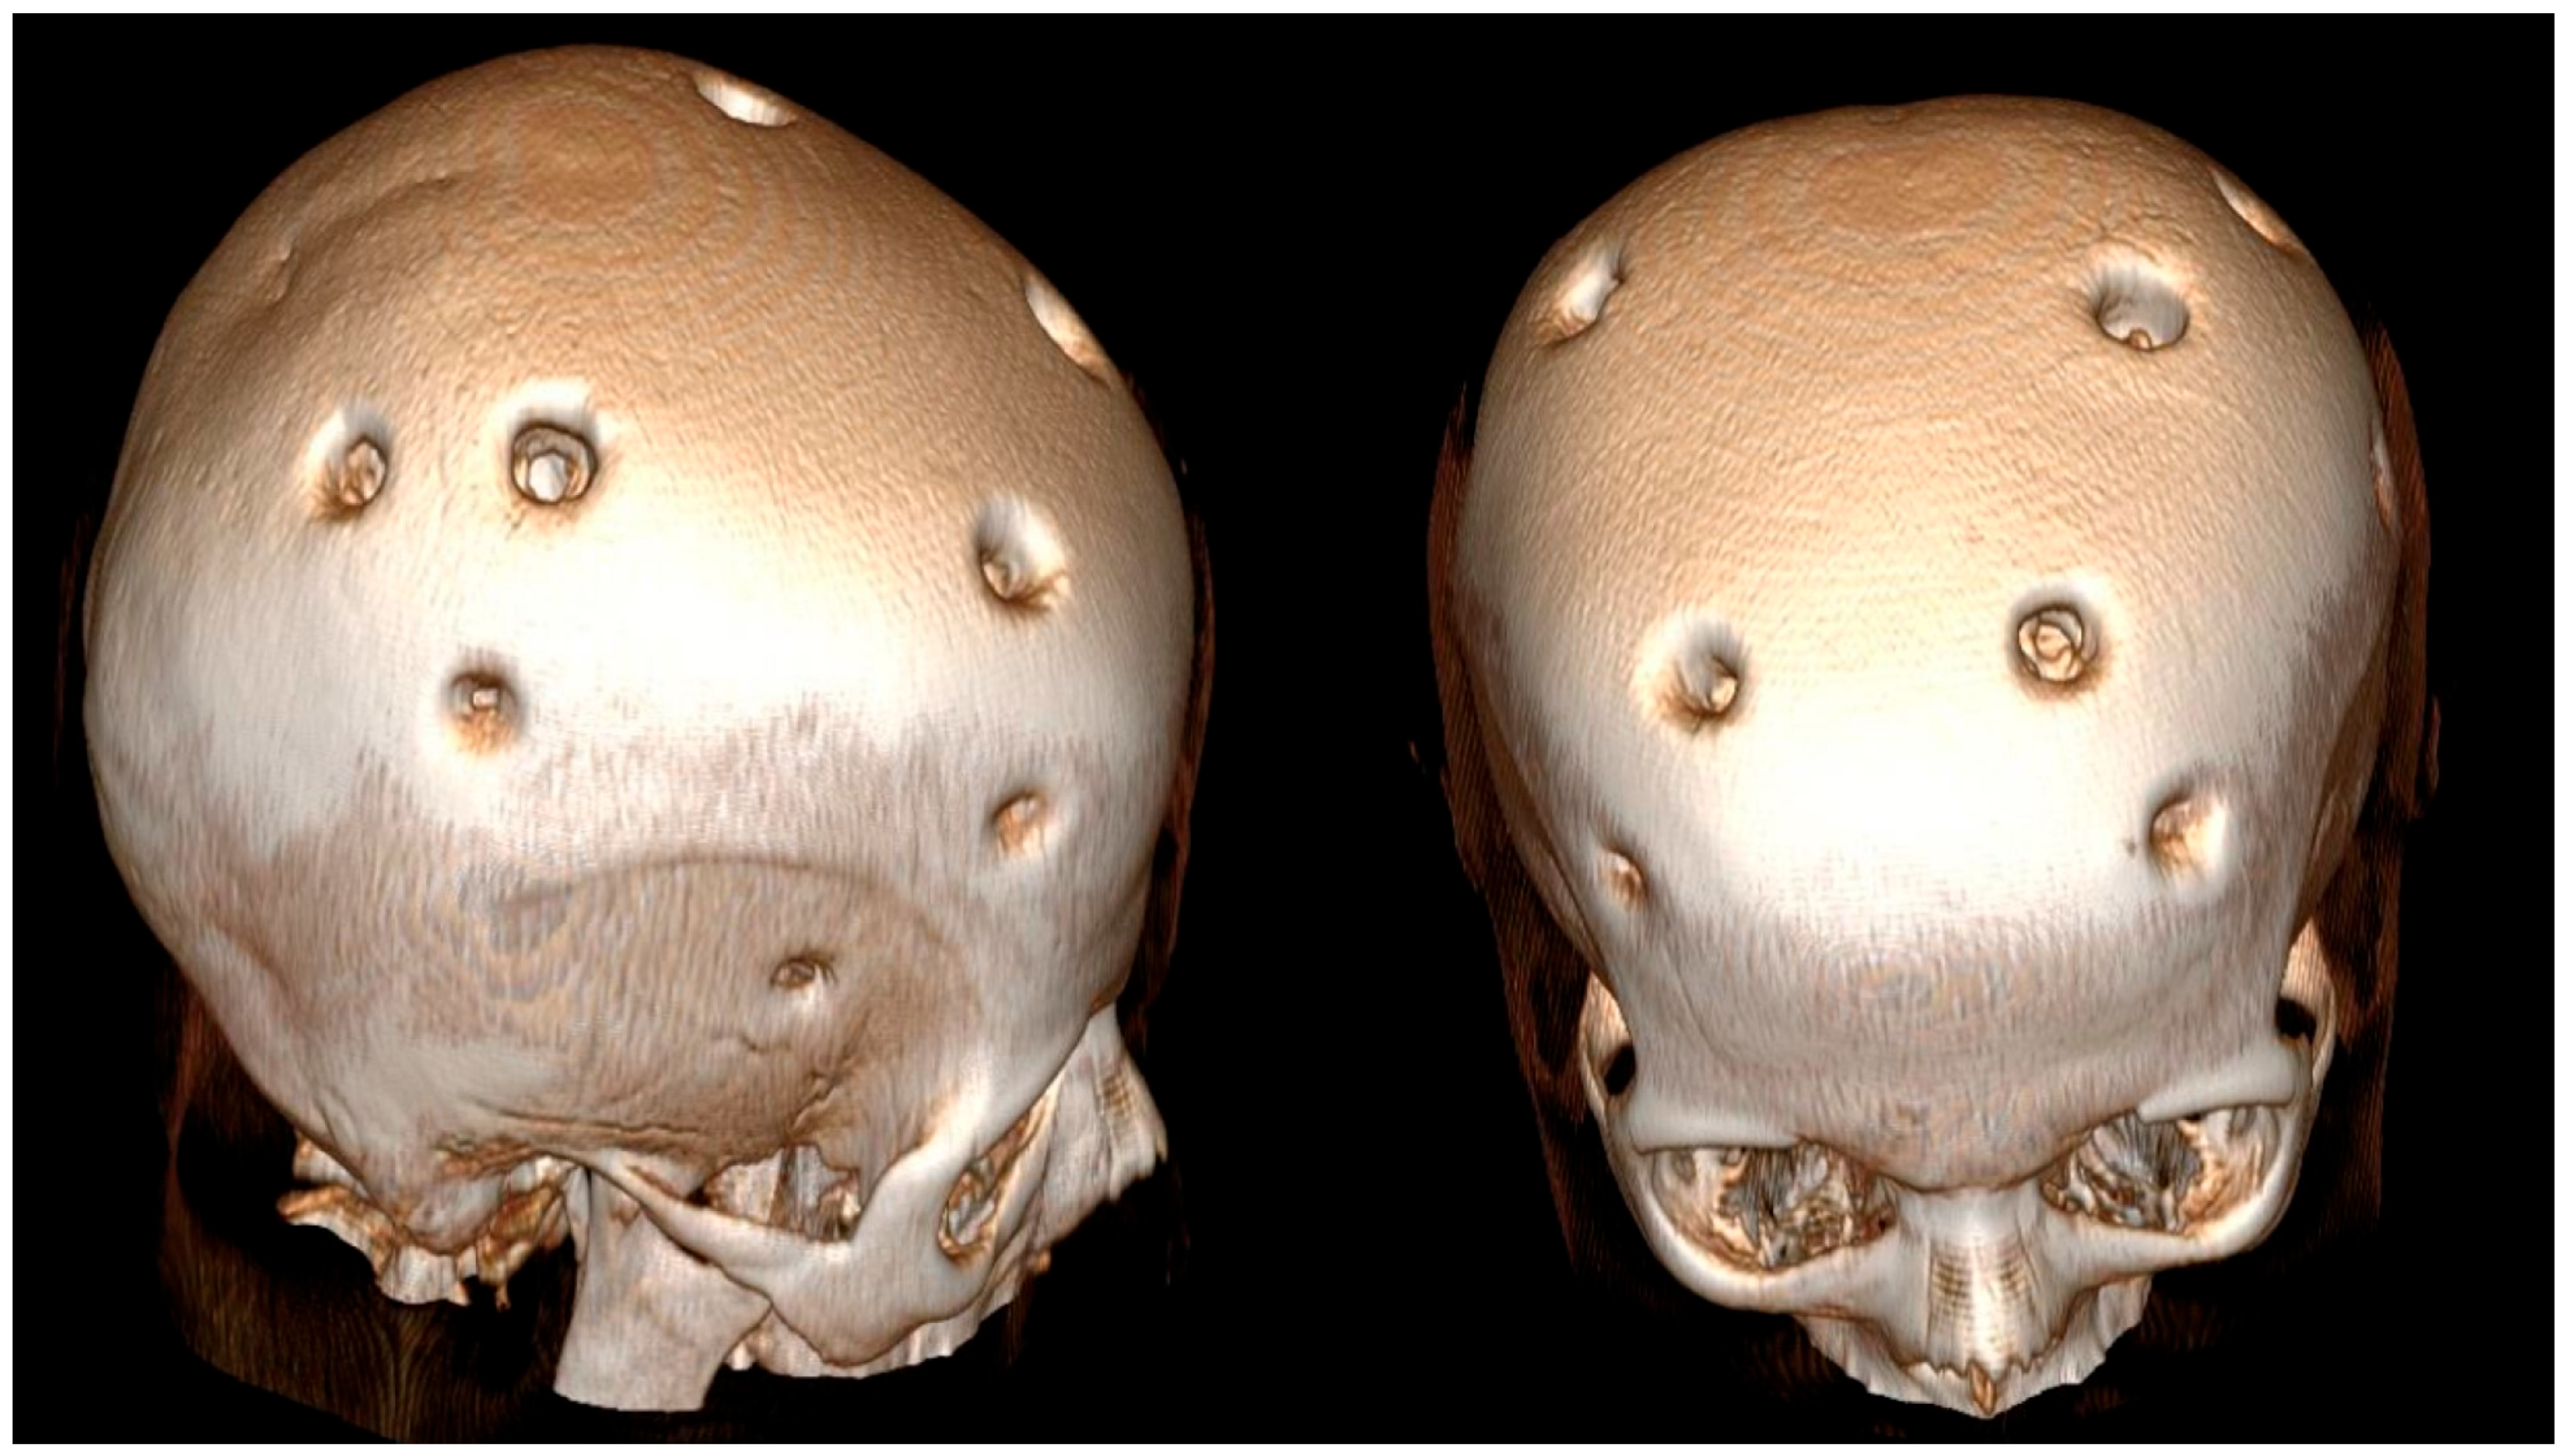

2. Case Description